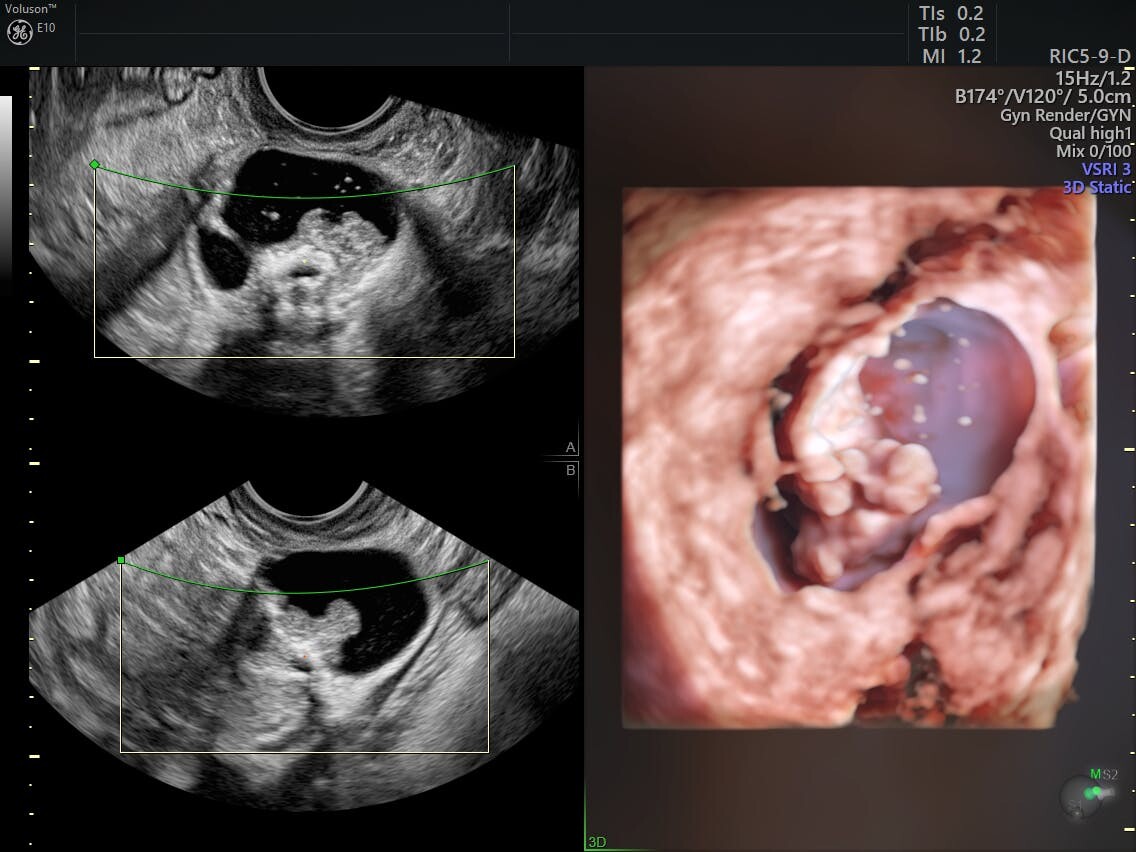

Adneksiyal kitleler, doktorların uterus, yumurtalıklar ve fallop tüplerini içeren vücudun bir parçası olan uterusun ekinde bulabilecekleri kitlelerdir. Tüm topaklar kanserli değildir ve hepsi tedavi gerektirmez. Farklı tipte aksesuar blokları aynı semptomların çoğunu paylaşabilir. Sonuç olarak, doktorların tam bir tıbbi geçmiş ve fizik muayene, kan testleri ve transvajinal ultrason da dahil olmak üzere tıbbi görüntülemeden elde edilen verileri toplaması gerekir. Doktorların uygun tedaviyi belirlemek için bir adneksiyal kitlenin yerini ve nedenini belirlemesi gerekir.